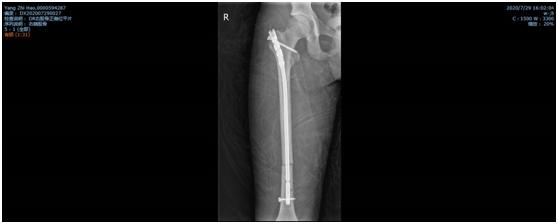

经过骨二科全科人员的商讨后,全麻下行闭合复位髓内钉内固定术的手术方案基本确定。但就国内目前而言,有关髓内钉固定治疗骨骼未成熟的股骨干骨折的疗效研究的样本较小。而且,孩子身高仅160cm,形体偏瘦,测量股骨髓腔最细处约6-7mm,而成人最细髓内钉髓直径大约9mm,无法使用。王钦楠主任积极联系厂家及器械公司,适合的髓内钉终于及时到位,在克服一系列困难及相关科室的支持下,作为威海市首例、山东省第二例同类手术,顺利完成,患者目前已开始负重功能锻炼,病情恢复良好。

双侧股骨干骨折术后照片